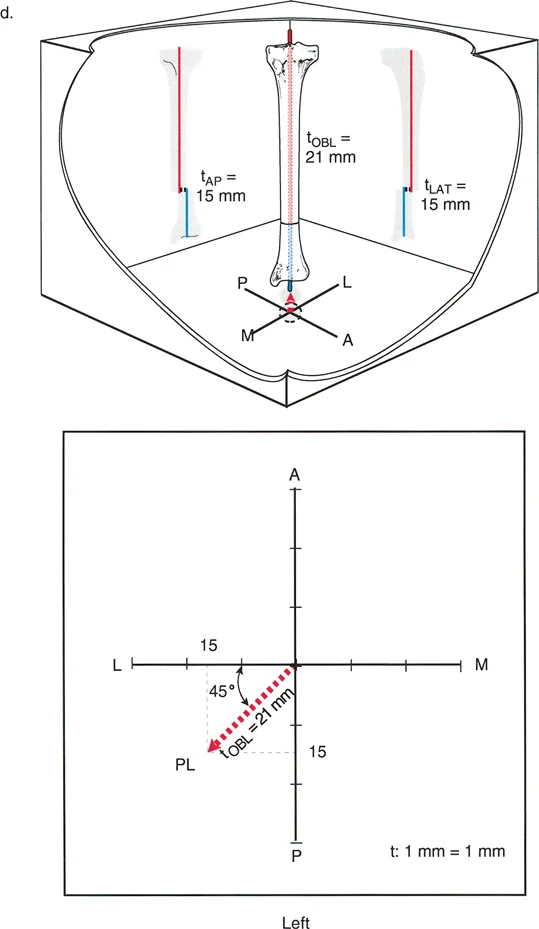

3. الرسوم البيانية للانزياح (Translation Graphs)

يستخدم الأستاذ الدكتور محمد هطيف رسوماً بيانية خاصة لتحليل تشوهات الانزياح، خاصة تلك التي تحدث في المستويات المائلة. هذه الرسوم البيانية تساعد في:

* تحديد الاتجاه الدقيق: مثل الاتجاه الأمامي-الخلفي (AP) أو الإنسي-الوحشي (LAT) أو مزيج منهما (Posterolateral - PL).

* قياس الحجم بدقة: تسمح بقياس حجم الانزياح بالمليمترات، حتى في المستويات المعقدة.

* تحديد مستوى الانزياح: المسافة من المفصل القريب إلى مستوى التداخل.